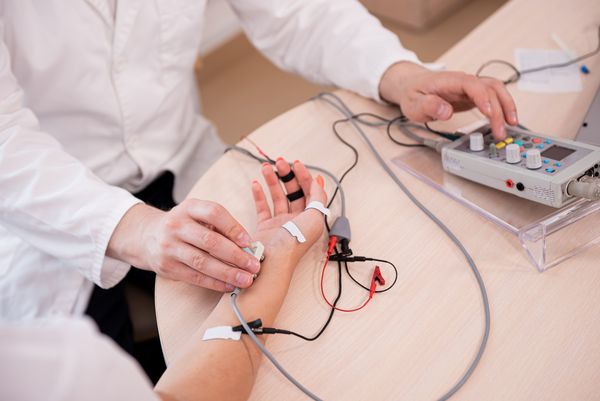

Для определения уровня и степени поражения нервного волокна выполняется электромиография (ЭМГ). При необходимости может быть проведена стимуляционная ЭМГ (на поверхность кожи накладываются электроды) или игольчатая ЭМГ (в исследуемую мышцу вводятся электроды-иглы).[1]

Электронейромиография